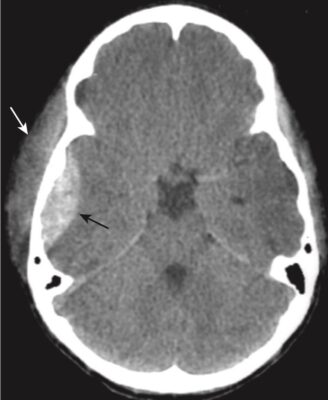

- Nhận biết máu tụ dưới màng cứng cấp tính (Hình 9)

- Trên CT, máu tụ dưới màng cứng cấp tính có hình lưỡi liềm, các dải ngoài não có đậm độ cao có thể băng ngang các đường khớp sọ và vào khe liên bán cầu. Máu tụ không vượt qua đường giữa.

- Điển hình, máu tụ dưới màng cứng lõm vào trong về phía não (máu tụ ngoài màng cứng lồi vào trong) (xem Hình 9, A).

- Sau một thời gian và khi máu tụ chuyển sang bán cấp, hoặc nếu máu dưới màng cứng được trộn với dịch não tủy có độ đậm đặc thấp hơn, chúng có thể biểu hiện đồng tín hiệu/cùng đậm độ (isodense) so với phần còn lại của não, trong trường hợp đó cần tìm các rãnh não bị ép hoặc biến mất hoặc bị đẩy lệch khỏi mặt trong xương sọ như các dấu hiệu của SDH (xem Hình 9, B).

- Các máu tụ dưới màng cứng có thể biểu hiện một mức dịch- dịch sau 1 tuần, khi các tế bào lắng xuống dưới huyết thanh.

- Máu tụ dưới màng cứng mạn tính thường có đậm độ thấp so với phần còn lại của não (xem Hình 9, C).